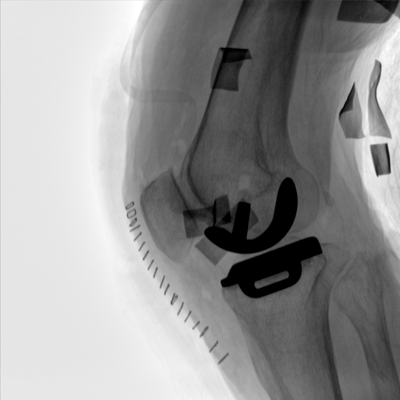

圖形化操控界面設(shè)計:設(shè)有多種人體特征攝影參數(shù),操作簡便。雙向紅光十字定位系統(tǒng):實現(xiàn)無射線下的高效定位。信息共享:遵循DICOM3.0格式接口,可無縫對接云PACS系統(tǒng)。

多角度自由旋轉(zhuǎn),滿足患者復(fù)雜擺位需求。